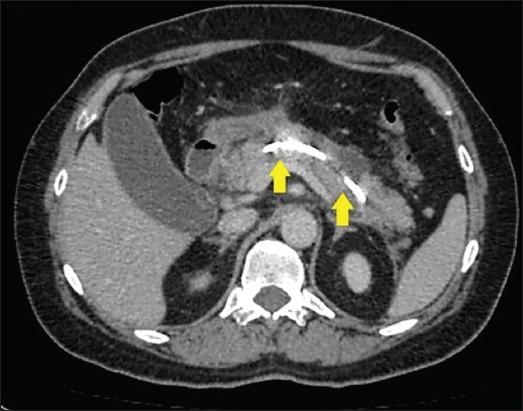

Pancreatic ascites is a rare condition characterized by the accumulation of high-amylase ascitic fluid in the peritoneal cavity. This condition is often associated with chronic pancreatitis, pancreatic trauma, or pseudocyst rupture. Because of its rarity and ill-defined clinical presentation, pancreatic ascites is often a diagnostic and therapeutic challenge in clinical practice. The current diagnostic criteria include an amylase level >1000 mg/dL, a protein level >3 g/dL, and a serum ascites albumin gradient <1.1 g/dL. The clinical features vary, but may include progressive abdominal distension, diffuse abdominal pain, weight loss and peritonitis. The management of pancreatic ascites remains controversial, and there is no consensus regarding the optimal approach. Conservative medical management, which includes nutritional support, pain control, therapeutic paracentesis and the use of somatostatin analogs, has been associated with a high failure rate and significant morbidity. Interventional therapies, such as surgery and endoscopic transpapillary stenting, have shown more promising outcomes. However, the choice between these methods is still debated, with some advocating for endoscopic approaches, because of their minimally invasive nature and reduced morbidity compared with surgical options. Endoscopic approaches remain underutilized in practice, probably because of the need for repeated interventions, the potential risks associated with endoscopic retrograde cholangiopancreatography, or a lack of skilled personnel. Although they show significant perioperative morbidity and mortality, surgical options provide definitive resolution of pancreatic ascites. Herein, we provide an updated review of pancreatic ascites, highlighting advances in diagnostic techniques and therapeutic approaches, and summarizing insights from recent clinical cases and retrospective studies.

胰源性腹水是一种罕见病症,其特征为腹腔内积聚高淀粉酶含量的腹水。这种病症常与慢性胰腺炎、胰腺创伤或假性囊肿破裂相关。由于其罕见性及临床表现不明确,胰源性腹水在临床实践中往往是诊断和治疗上的一大挑战。目前的诊断标准包括淀粉酶水平>1000毫克/分升、蛋白质水平>3克/分升以及血清腹水白蛋白梯度<1.1克/分升。临床特征各异,但可能包括进行性腹胀、弥漫性腹痛、体重减轻和腹膜炎。胰源性腹水的管理仍存在争议,对于最佳治疗方法尚无共识。保守药物治疗,包括营养支持、疼痛控制、治疗性腹腔穿刺放液及使用生长抑素类似物,其失败率较高且发病率显著。介入治疗,如手术和内镜下经乳头支架置入术,已显示出更有前景的结果。然而,这些方法之间的选择仍存在争议,一些人主张采用内镜方法,因为其微创性质以及与手术选择相比发病率较低。内镜方法在实践中的应用仍然不足,可能是因为需要重复干预、与内镜逆行胰胆管造影相关的潜在风险,或缺乏技术熟练的人员。尽管手术选择显示出显著的围手术期发病率和死亡率,但能为胰源性腹水提供确定性的解决方案。在此,我们提供胰源性腹水的最新综述,强调诊断技术和治疗方法的进展,并总结近期临床病例和回顾性研究的见解。